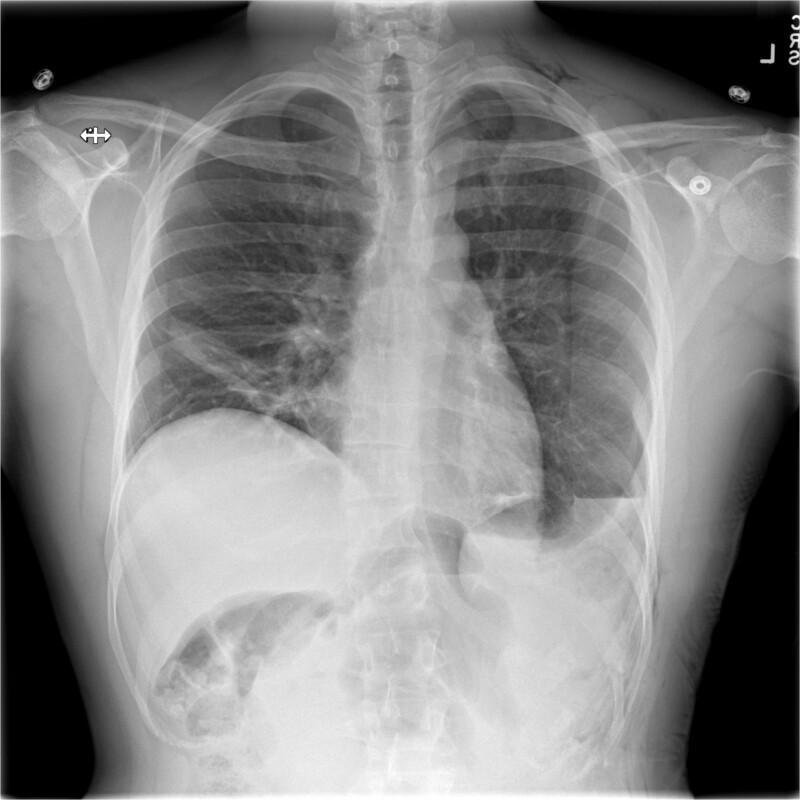

Gastric volvulus has been rarely associated with diaphragmatic paralysis or eventration. In this article, we present the case of a patient with idiopathic paralysis of the left hemidiaphragm that underwent treatment with a robotic thoracoscopic diaphragm plication, which was complicated by massive gastric volvulus resulting in such significant intra-abdominal hypertension that the ipsilateral diaphragm ruptured anterior to the plication suture line.

胃扭转很少与膈麻痹或膈膨出相关。在本文中,我们报告了一例特发性左半膈麻痹患者,该患者接受了机器人胸腔镜膈折叠术治疗,术后并发大量胃扭转,导致严重的腹腔内高压,使得同侧膈肌在折叠缝线前方破裂。